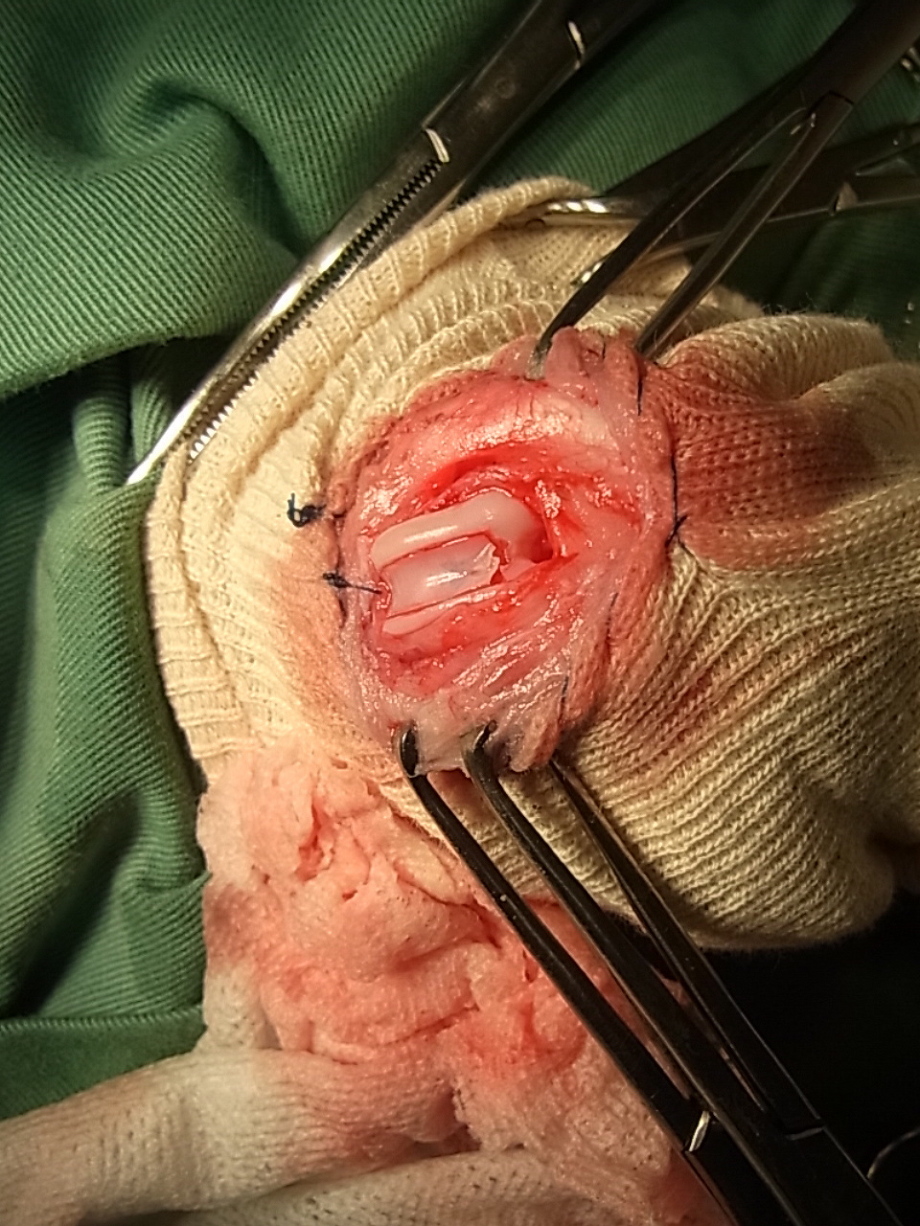

関節包を縫合したところです。関節包は強度があまりありませんので縫縮する必要はありません。

外側の筋膜を鱗状に被せ膝蓋骨を覆うように縫合し外側にテンションがかかるように縫縮します。